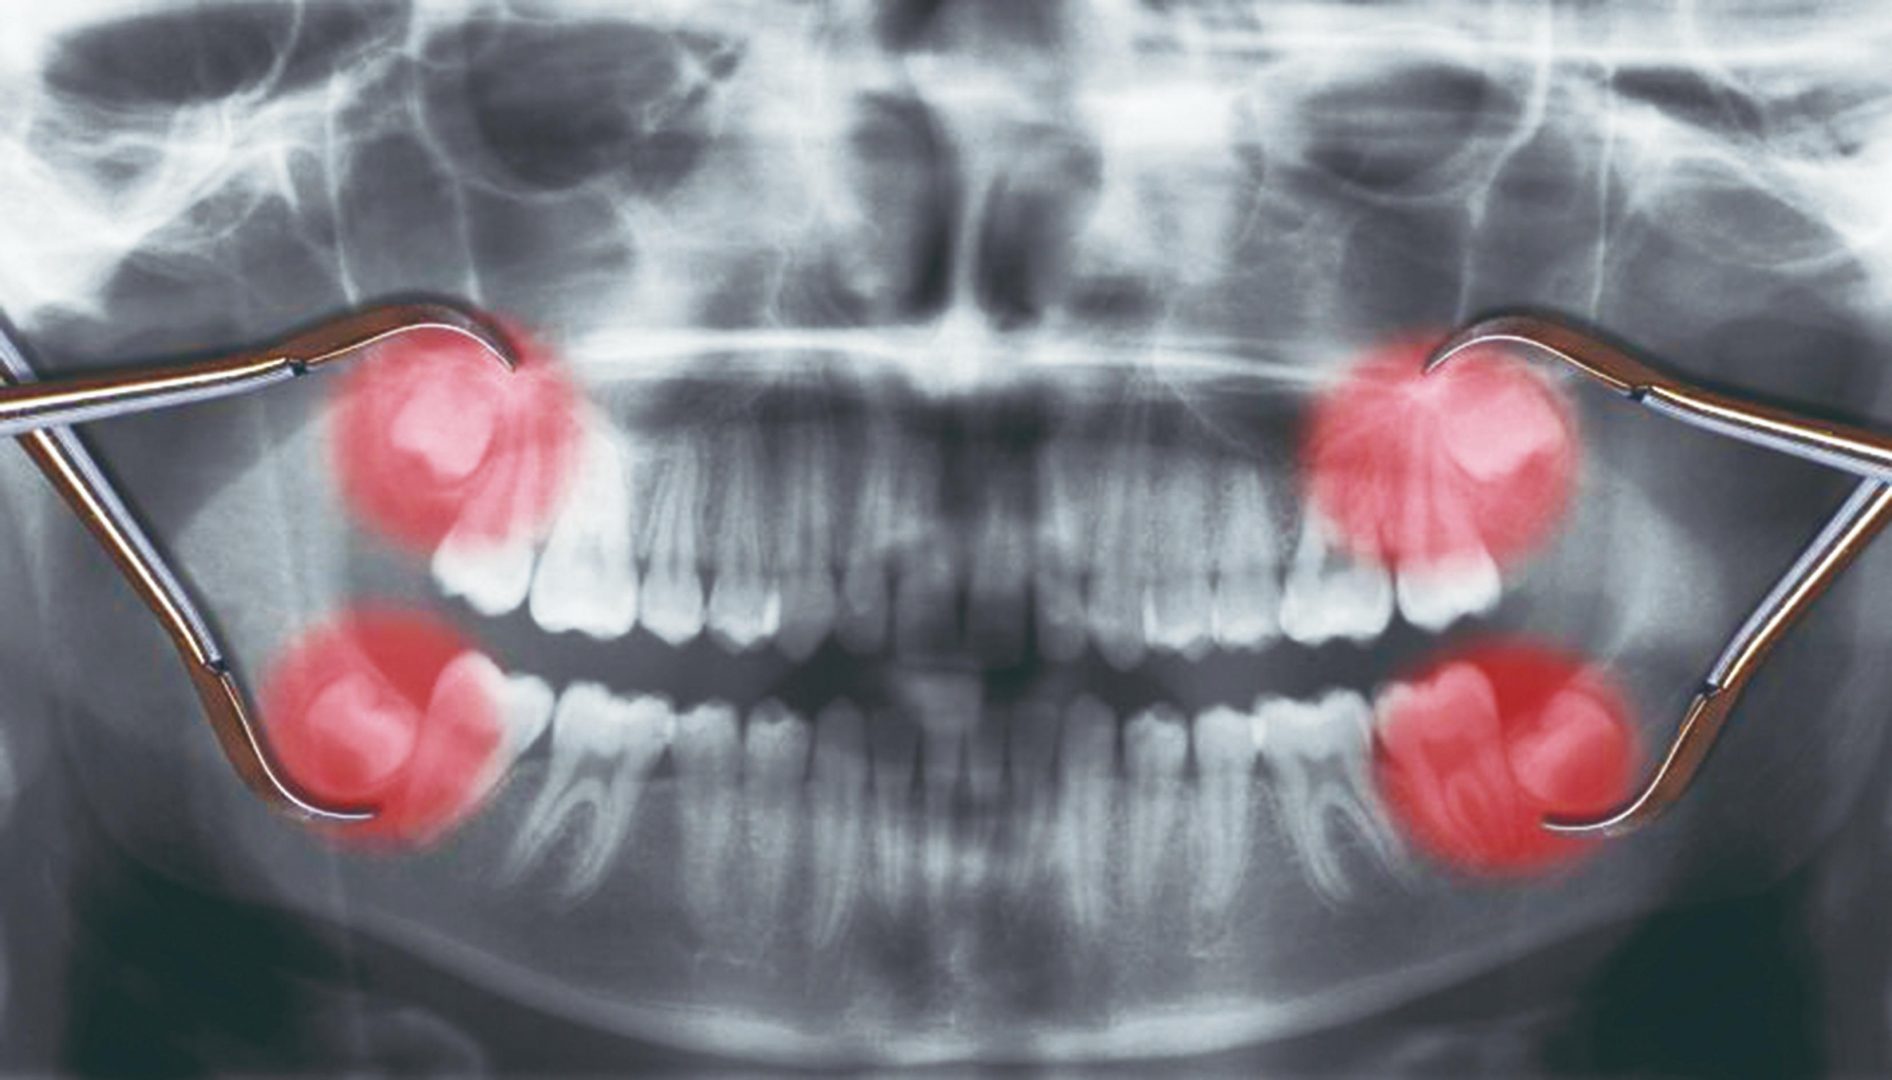

Todo mundo tem quatro sisos?

Não. Há pessoas que podem não apresentar nenhum deles ou todos. Em alguns casos, o dente até pode estar ali – mas a erupção não ocorre. Mas, na maioria das vezes, surgem os quatro sisos mesmo: dois superiores e dois inferiores.

É possível retirar os quatro sisos de uma vez?

Na verdade, não só é possível como, em geral, é preferível. Afinal, como o pós-operatório demanda repouso, uso de medicação e dieta especial — entre outras coisas — o melhor mesmo é vivê-lo só uma vez.